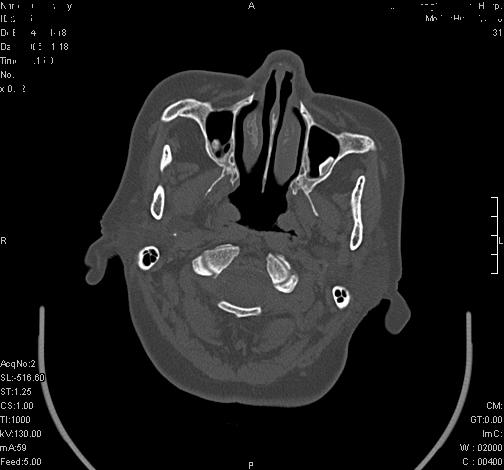

上次发的片子,不够细微。误导了大家,请大家再重新看一下,思路会更清晰。

双上颌窦高密度,其内见水样密度.考虑双上颌窦骨瘤伴上颌窦炎.

双上颌窦高密度,左侧病灶下部与左上颌窦底部骨质相延续,支持双上颌窦骨瘤

双侧上颌窦上部黏膜明显增厚、窦腔缩小,偏后侧窦壁骨质毛糙、模糊,窦腔内见条块状钙化。结合双侧鼻甲黏膜明显增厚,以及临床症状,

考虑:双侧上颌窦霉菌性鼻窦炎

双侧上颌窦密度增高,粘膜增厚,内见条片状钙化,窦壁无增生与破坏征象,双侧鼻甲粘膜肥厚.

意见:双侧霉菌性上颌窦炎.

温习:真菌性鼻旁窦ct特征 1)非侵袭性病变者可涉及到鼻腔和鼻窦,多为单侧,上颌窦最多见.2)ct示窦腔内软组织增生影,可呈息肉状,+c可强化3)增生软组织影内可见散在斑片状或沙砾状钙化区,此为其典型特点,4)

非侵袭性病变可见窦壁骨质增生,破坏少见;侵袭性病变可见窦壁骨质破坏.